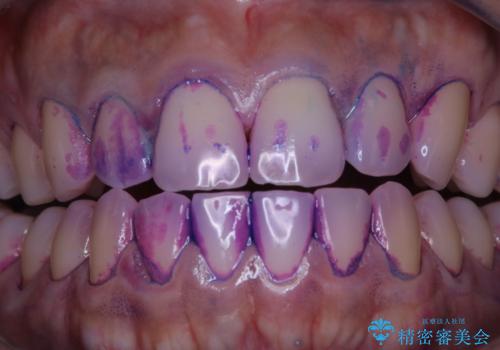

実はこんなに磨き残しが!!!

- 半年ぶりにクリーニングを希望とのことでした。

染め出しをしての磨き残しチェックとPMTC60分コースを行いました。

しかし、プラークは歯の色と似ているため、見ただけでは付着しているかどうかがハッキリとは分かりません。

染め出し液を使ってプラークを染め出すことにより、普段の歯みがきで磨き残している場所を目で確かめることができます。

日々の歯磨きを上達するには、まずどこが磨けていないか認識することが大切です。